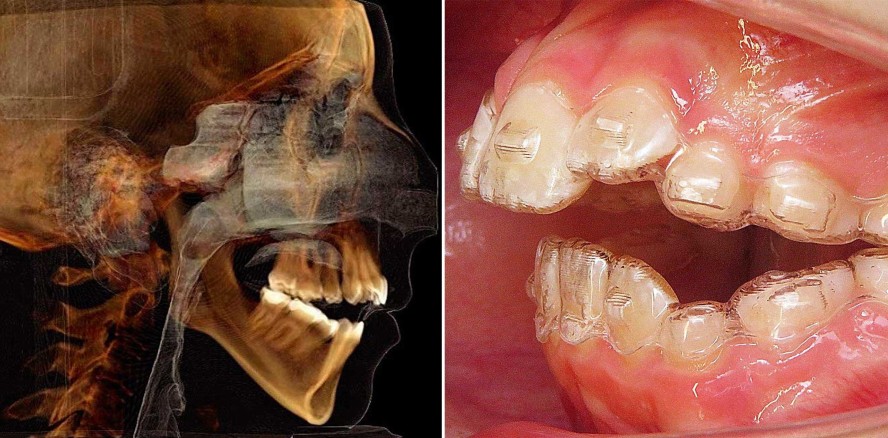

Die Therapie des offenen Bisses, sei er primärskelettaler oder überwiegend funktioneller Genese, aber auch häufig in Kombinationen vorliegend, stellt an den Behandler generell eine gewisse Herausforderung dar. Bei einem sehr ausgeprägten vertikalen Wachstumstyp mit stark divergierenden Kieferbasen sind es oftmals die biomechanischen und anatomischen Limitationen, die ab einem gewissen Ausprägungsgrad nicht nur eine rein kieferorthopädische, sondern eine kombiniert kieferorthopädisch-kieferchirurgische Intervention indiziert erscheinen lassen. Dies trifft insbesondere bei erwachsenen Patienten zu, bei denen eine frühzeitige Therapie oftmals unterlassen oder nicht effizient genug durchgeführt wurde. Die Abbildungen 1a und b zeigen in der FRS-Darstellung eine solche ausgeprägte gnathisch offene Gesichtskonfiguration im prä- und postoperativen Stadium bei bimaxillärer Umstellungsosteotomie einer 34-jährigen Patientin. Diese Therapieform erfordert neben der orthodontischen Zahnbewegung durch den Kieferorthopäden immer auch eine enge Kooperation mit dem Kieferchirurgen bezüglich Planung und Therapiedurchführung. Dieser Casus wurde ausführlich in der KN-Ausgabe 7+8 / 2020 vorgestellt. Ist die Ursache des offenen Bisses primär im Vorliegen funktioneller Dysbalancen zu sehen, so ist eine möglichst frühzeitige und oftmals auch interdisziplinäre Intervention indiziert. Die aktuelle S3-Leitlinie der Fachgesellschaften definiert den idealen Behandlungszeitpunkt bei kieferorthopädischen Anomalien im Milch- und frühen Wechselgebiss, also vor dem zehnten Lebensjahr, „als Prävention sich anbahnender Kieferfehlbildungen, zur Hemmung skelettaler Wachstumsanomalien bzw. der Beseitigung manifester Anomalien mit Funktionsstörungen, die sich bei Nichtbehandlung verschlimmern könnten“.1

Eine Mutter stellte ihre achteinhalbjährige Tochter Mitte letzten Jahres in unserer Praxis vor. Die kleine Patientin zeigte bereits äußerlich den Genotypus einer schmalen, deutlich vertikalen Gesichtskonfiguration bei einer hypotonen Orafazialmuskulatur mit angestrengtem Lippenschluss (Abb. 2a–d). Zu diesem Zeitpunkt befand sich das Mädchen zu Beginn seiner zweiten Wechselgebissphase, alle bleibenden Zähne, bis auf die dritten Molaren, waren angelegt, wie im Orthopantomogramm zu sehen ist (Abb. 3a). Durch das viszerale Schluckmuster zeigten die unteren Inzisiven bei schmaler apikaler Basis eine deutliche Retroinklination, während bedingt durch die Zungeninterposition die oberen Frontzähne lückig anteinkliniert positioniert sind. Die Fernröntgenseitenaufnahme lässt bei einer skelettalen Klasse II-Relation und einem ausgeprägt divergierenden Basiswinkel die Frontzahninklinationen mit dem deutlich frontal offenen Biss gut erkennen (Abb. 3b). Noch imponierender erscheint beim klinischen Funktionsbefund der dysfunktionale Einfluss der Zunge aufgrund eines persistierenden, viszeralen Schluckmusters mit auffälliger Zungeninterposition (Abb. 4).